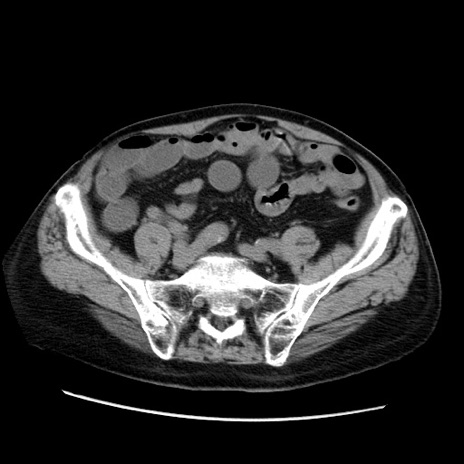

症例21(横断像)

【症例】70歳代男性

【主訴】腹痛

【現病歴】肝硬変・肝細胞癌にてかかりつけの方。約9時間前に食後より腹痛出現。症状が徐々に増悪し、嘔吐出現したため来院。

【既往歴】肝硬変、肝細胞癌(RFA、TACE後)

【身体所見】意識清明、表情苦悶様、BT 36℃、BP 129/78mmHg、P 88bpm、SpO2 97%(RA)、右上腹部から心窩部にかけて圧痛あり、反跳痛なし、筋性防御あり。

【データ】WBC 5800、CRP 0.16